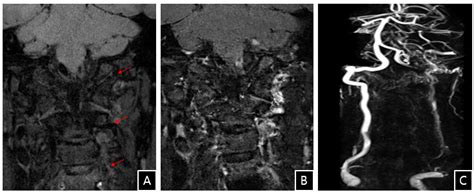

Because Vertebral Artery Dissection Symptoms often overlap with common ailments like migraines, physicians must maintain a high index of suspicion. Diagnostic imaging is the gold standard for confirming a suspected dissection. Medical professionals typically use advanced techniques such as CTA (Computed Tomography Angiography) or MRA (Magnetic Resonance Angiography) to visualize the arterial walls. These scans allow doctors to see the “flap” of the torn artery or the presence of a hematoma within the vessel wall. Early intervention, usually involving antiplatelet or anticoagulant therapy, is aimed at preventing the formation of clots that could lead to a stroke.

• vertebral artery dissection radiology

• vertebral artery dissection mra